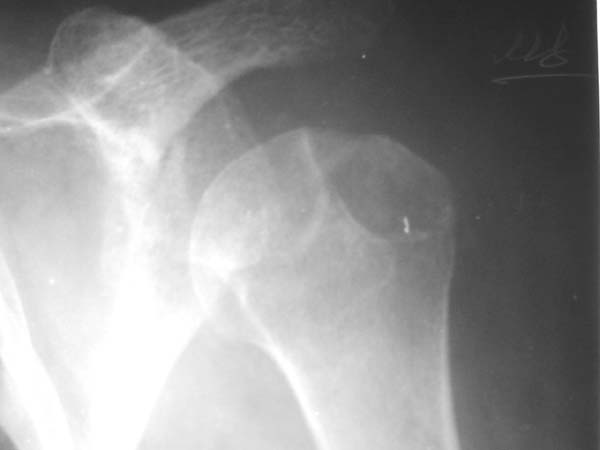

Re: Вывих плеча

> Непонятный очаг по заднему контуру

> Именно этот участок и смущает больше всего.

"Прицельная" съемка малопонятного очага.

В приложенном файле - МРТ изображение. Более информативно, чем предыдущий вариант? менее? или также?